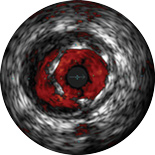

ChromaFlo обеспечивает простую оценку аппозиции стента, размера просвета сосуда и других параметров за счет выделения кровотока красным цветом на изображении в одно нажатие кнопки. Функция ChromaFlo доступна на системах для интервенционных вмешательств Philips.

Эта функция создана для быстрой оценки размера просвета сосуда и аппозиции стента; она облегчает определение ветвей сосудов, диссекций и тромбов, а также упрощает оценку распределения бляшек в области бифуркаций. Функция ChromaFlo выделяет кровоток красным цветом, что помогает:

Во время визуализации не требуется выполнять промывание или какие-либо специальные процедуры. Просто активируйте функцию ChromaFlo одним нажатием кнопки.

Функция ChromaFlo совместима с цифровыми катетерами для ВСУЗИ Philips Eagle Eye Platinum.